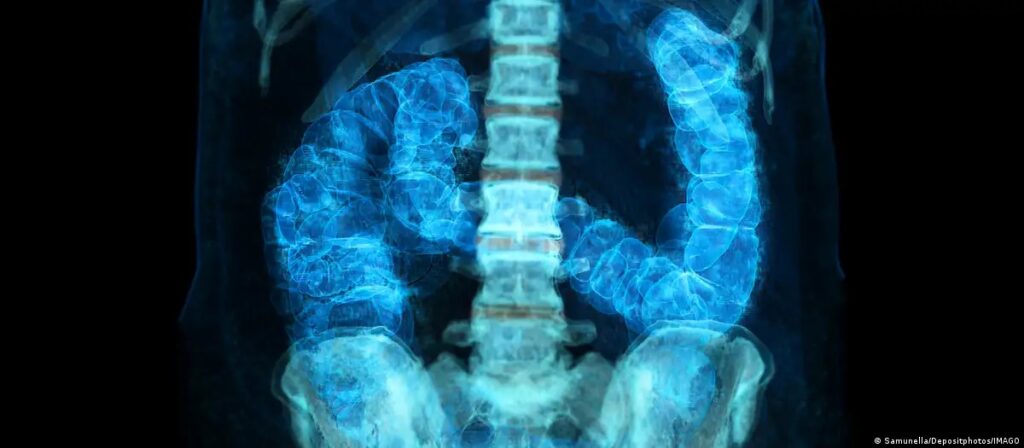

Câncer no intestino avança entre americanos menores de 50 anos

Samunella/Depositphotos/IMAGO

Incidência aumenta entre menores de 50 anos, e especialistas buscam respostas para o avanço precoce da doença. No Brasil, mortes devem crescer 36% até 2040.O câncer colorretal, antes associado sobretudo a adultos mais velhos, avança cada vez mais entre homens e mulheres jovens. Nos Estados Unidos, já é a neoplasia que mais mata abaixo dos 50 anos.

Além disso, o local onde o tumor aparece ao longo do cólon, que tem formato semelhante a um ponto de interrogação, começando de um lado do abdômen, curvando‑se para o outro e terminando no reto, influencia sua agressividade e o tratamento.